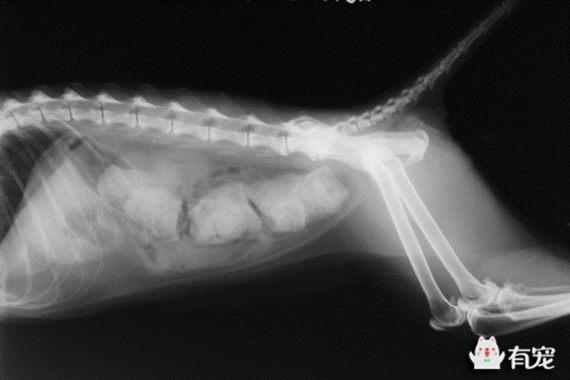

到了医院后医生先为大球进行了简单的物理检查,经过触诊,发现它的结肠内存有大量的粪便。随即医生又为大球做了X光,全项生化,血液常规等多项检查。通过对结果分析,大球被确诊患上了巨结肠症。

猫患上原发性或特发性巨结肠症的发生率远远高于犬,猫的特发性巨结肠症是由结肠平滑肌的功能障碍引起的。

对于患有巨结肠或完全性阻塞的便秘的猫咪,手术是必要的手段。手术主要有两种:在结肠开口取出大便,或者进行结肠完全/不完全切除。对于患有巨结肠的猫咪,通常兽医会建议进行完全性的结肠切除,因为巨结肠的复发率相当高,即使是在日常进行饮食及运动管理的猫咪,也免不了要面对非常高的复发风险。

谢谢大家关心,今天喵喵走了,很突然,突然呕吐然后就走了。之前完全没征兆,就在昨天还给它灌肠,今天上午表现也不错,我还满心欢喜的以为它要好了。看它跟我要拉手,还要踩奶,能吃能喝的,怎么也不像会突然离开的样子。真的很难接受。电话给宠物医院,对方提出解剖看看。不看不知道,原来我家喵喵有好多问题,一开腹腔全是腹水,而且是红色的,心脏和肺部都不好,之前的便秘医生说是巨结肠的原因就算治好,将来也是要复发的。本来我都盘算好将来无论多辛苦,我都养它一辈子。可我真看到它巨结肠时,很震惊,它在这段期间究竟受了多大的罪啊,肠子里满满的粪便,绕着肚子一圈一圈的。小家伙一直表现那么好,原来是骗我,怕我担心难过。这乖巧的小家伙,谢谢你陪了我一整个夏天,我很快乐,我爱你!